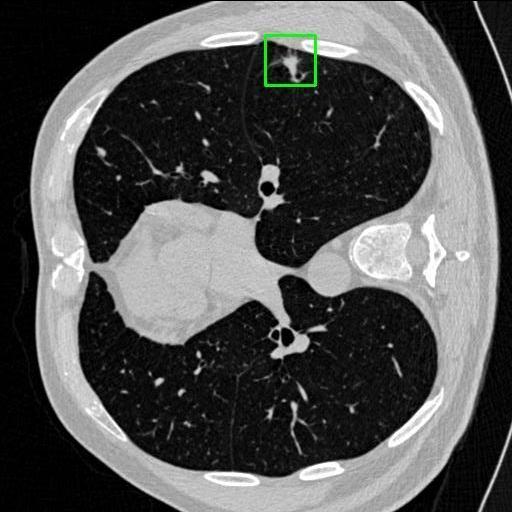

We developed an AI-based system using deep learning models for analyzing lung CT scans to detect and classify pulmonary nodules. We chose the YOLOv11 architecture for its enhanced object detection capability and adapted it specifically for medical imaging, incorporating pixel-level precision and severity classification.

Classification into three severity levels with colored bounding boxes.

Designed a severity classification system that categorizes nodules into null, moderate, and severe using colored bounding boxes, assisting in rapid clinical decision-making.